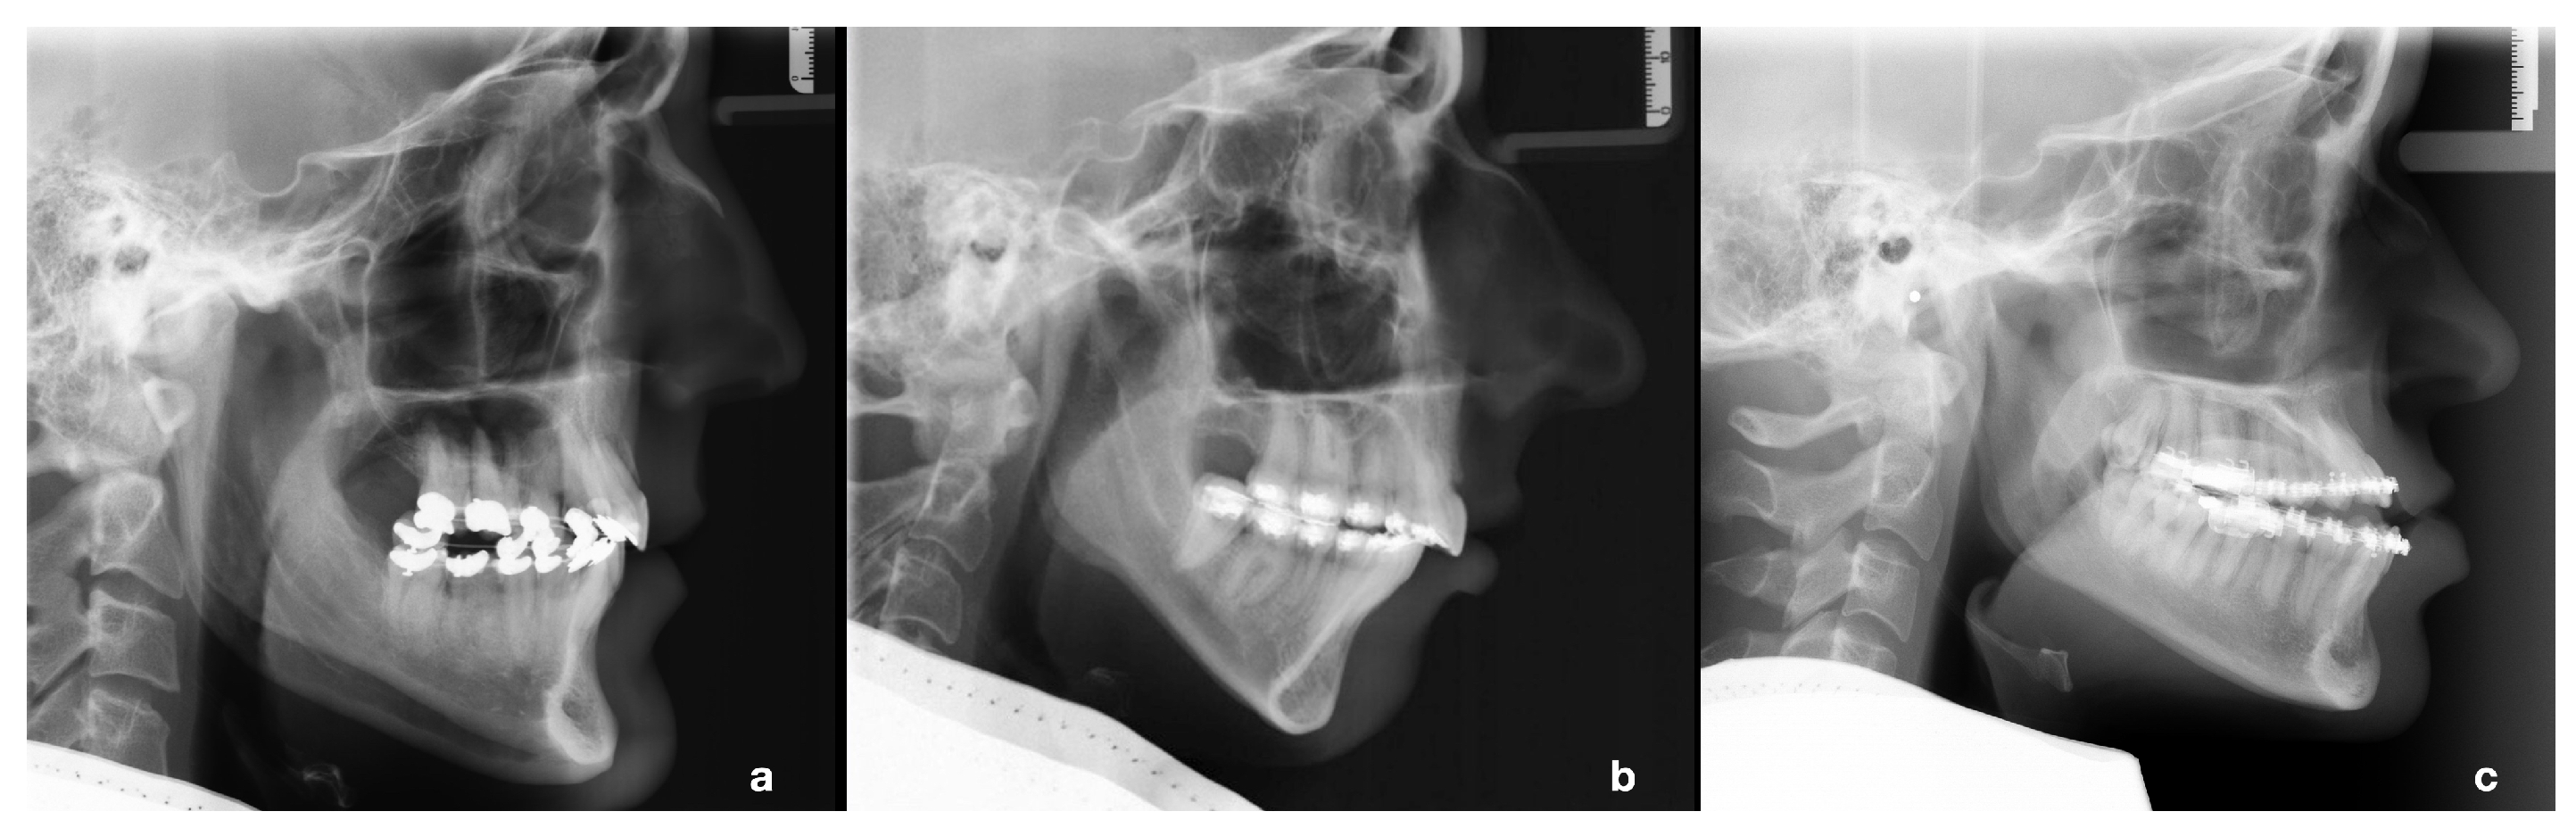

3.2. Cluster-Specific Skeletal Phenotypes

| Cluster | Skeletal Phenotype | AxV | AxH | |

|---|---|---|---|---|

| 1 | balanced face | 8 | 36 | 99 |

| 2 | vertical face, class II | 11 | 27 | 88 |

| 3 | horizontal face, class III | 2 | 36 | 86 |